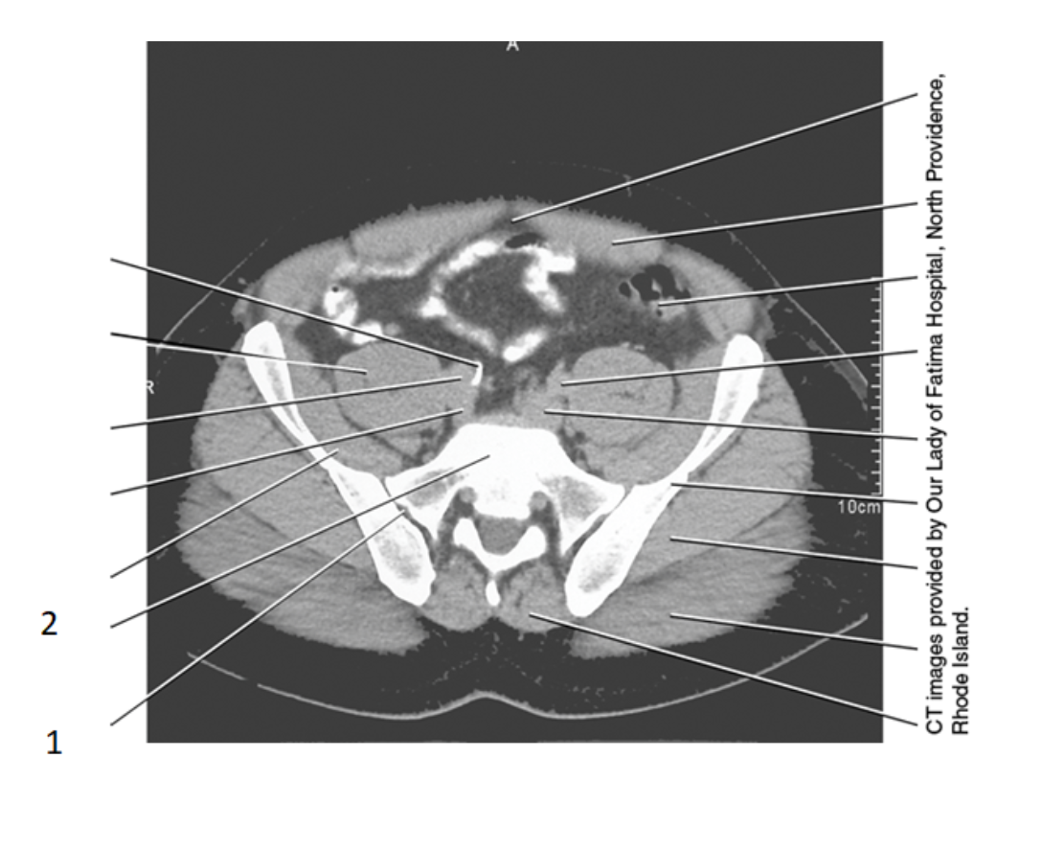

19

greater trochanter

15

femoral head

14

acetabulum

17

pubic bone

20

prostate

31

seminal vesicles

28

bladder

pubic symphysis

28 women

cervix

25 women

uterus